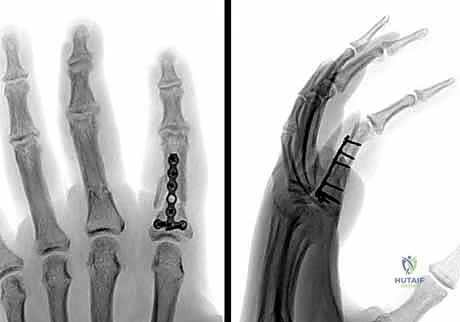

تقنيات التثبيت الجراحي الحديثة المتبعة في عيادة الدكتور هطيف

بفضل تخصصه الدقيق في جراحة العظام واليد، يستخدم الدكتور هطيف مجموعة واسعة من التقنيات الجراحية الحديثة، ويختار الأنسب لكل حالة:

2. الرد المفتوح والتثبيت الداخلي (ORIF - Open Reduction and Internal Fixation):

في الكسور المفتتة أو المعقدة، يقوم الدكتور هطيف بعمل شق جراحي دقيق (غالباً من الجانب لتجنب الأوتار الظهرية) لكشف الكسر وإعادة ترتيب الشظايا العظمية بدقة متناهية، ثم تثبيتها باستخدام:

* البراغي الساحبة (Lag Screws): تُستخدم في الكسور المائلة الطويلة أو الحلزونية لتوفير ضغط قوي بين حواف الكسر.

* الصفائح والبراغي الدقيقة (Mini-plates and Screws): تُستخدم في الكسور العرضية أو المفتتة لتوفير تثبيت صلب وقوي يسمح بحركة الإصبع في اليوم التالي للعملية.